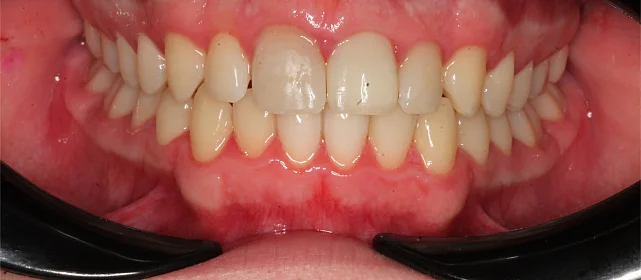

Результат

Прикус исправлен, зубы выровнены. Установлены несъёмные ретейнеры на обе челюсти, после установки коронок будут изготовлены ретенционные капы.

Решение: Установили металлические самолигирующие брекеты H4 на обе челюсти. За 28 месяцев выровняли зубы и привели прикус в норму. После снятия брекетов зафиксировали ретейнеры на обе челюсти. Пациентка направлена к ортопеду — в течение недели устанавливает коронки, после чего будет проведено сканирование и изготовлены ретенционные капы уже по окончательному контуру зубов.

Двухэтапный случай: сначала ортодонтия, потом протезирование. Ставить коронки при неправильном прикусе нельзя — нагрузка ляжет неравномерно, конструкции не прослужат долго. Брекеты H4 отработали за 28 месяцев, ряд подготовлен. Ретенционные капы сознательно делаем после коронок — контур зубов изменится, и капы должны соответствовать финальному результату.